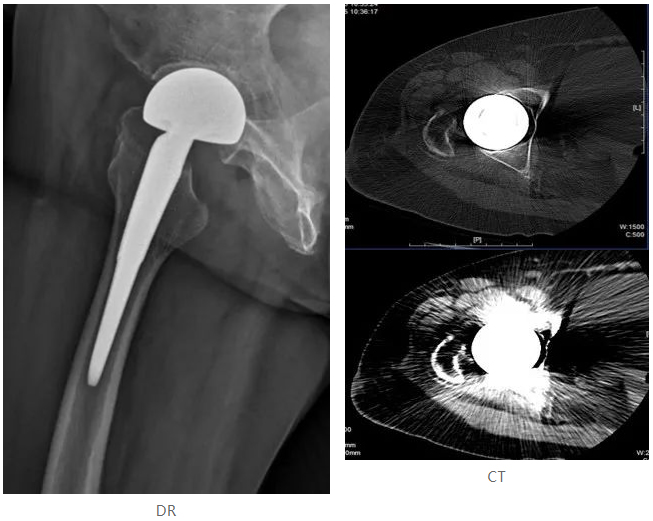

01 女,77岁,人工髋关节置换术后

3、 与CT相比,该检查方法在消除金属伪影方面有突出优势,且图像的空间分辨率高于CT图像,辐射剂量低于CT检查